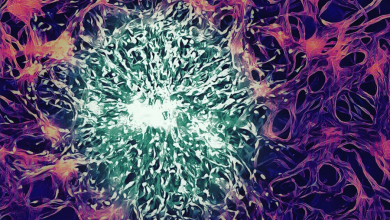

مطالعه جدید: تراشه جدید با باز کردن سد خونی به درمان سرطان مغز کمک میکند

سد خونی مغزی یا همان «BBB» یک خط دفاعی حیاتی برای ایمن نگه داشتن مغز از سموم بدن است. اما…